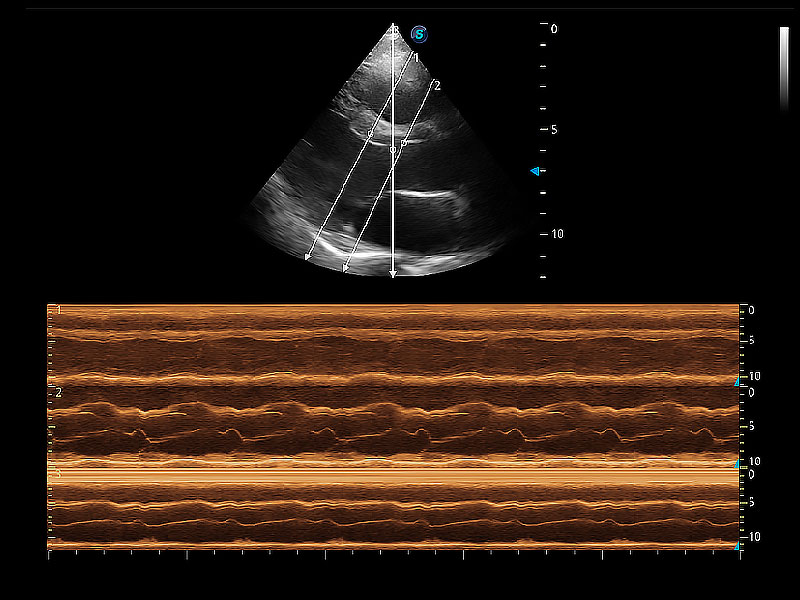

通过360度任意调节3条M型取样线,在同一心动周期上观察心脏不同位置的运动曲线,得到准确的心功能测量数据,有效评估心肌运动及左心室功能。